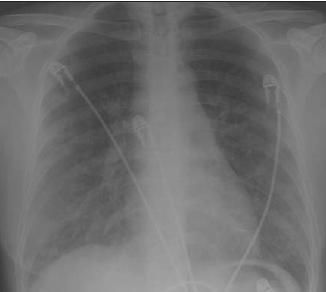

A chest radiograph showed bilateral alveolar infiltrates with peripheral predominance in both lungs (Figure 1). A CT scan of the chest showed extensive alveolitis, with lobular ground-glass opacities and thickening of the interlobular septa (Figure 2). The patient was found to have eosinophilia with an absolute eosinophil count of 750/μL, which amounted to 7% of her peripheral white blood cell count.

Figure 1 – Bilateral alveolar infiltrates with peripheral predominance in both lungs can be seen on the patient's chest radiograph.